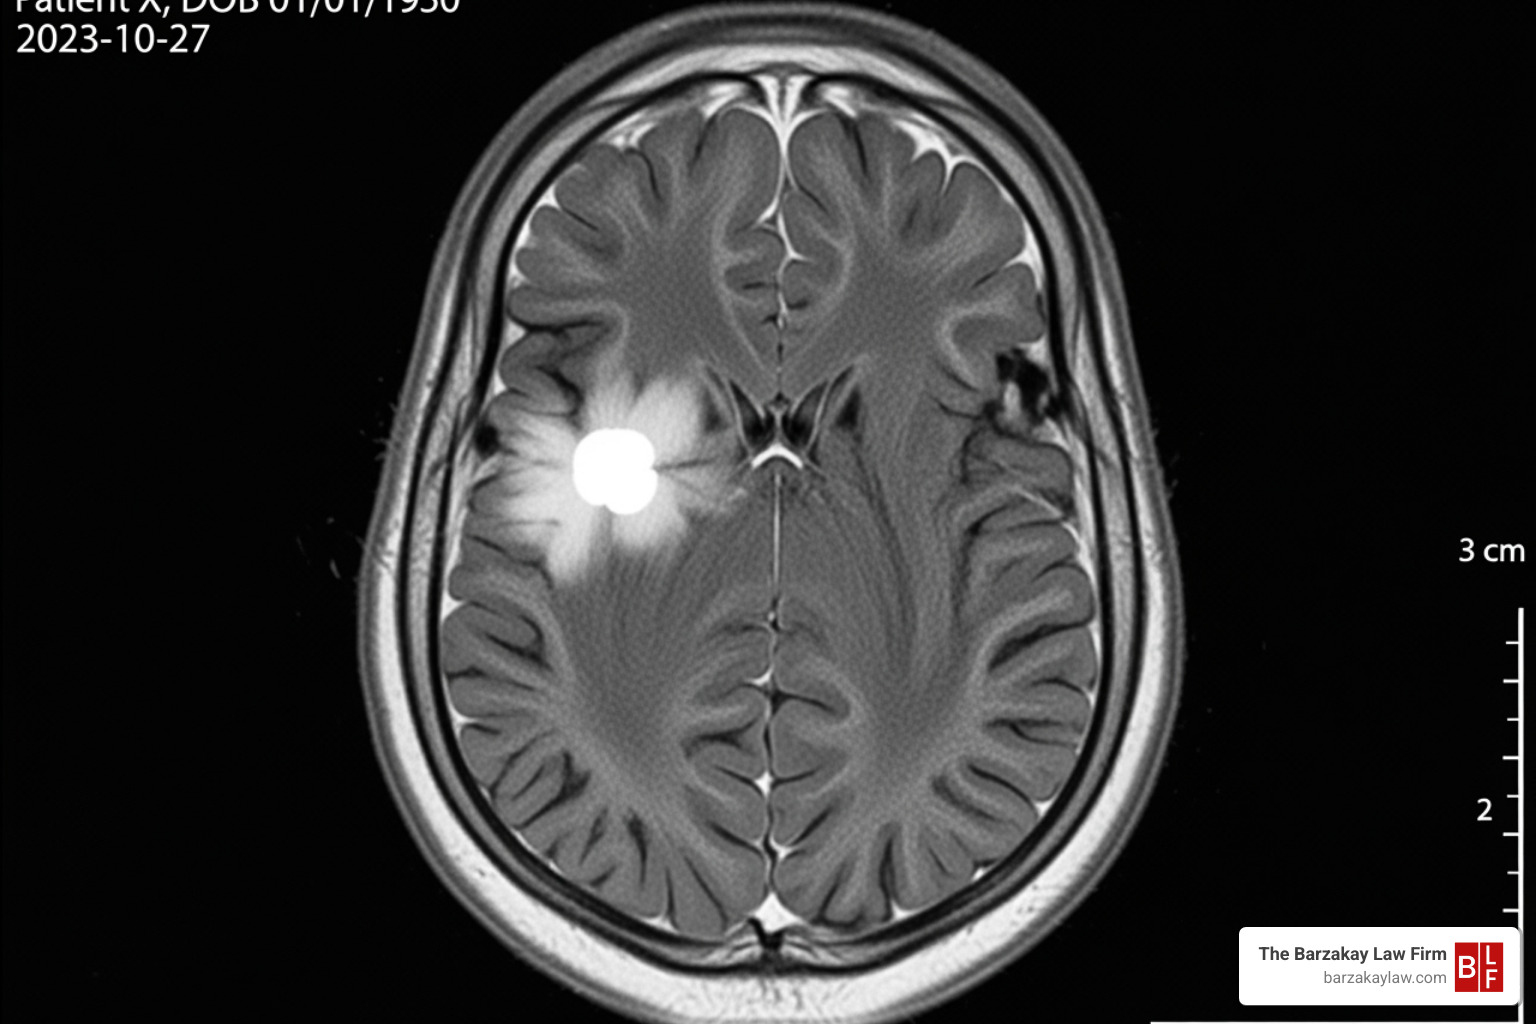

- Misreading lab results or imaging scans

- Misinterpreting lab results or imaging scans, which can be as harmful as not ordering the tests at all.

Early cancer detection is key to survival. When providers in Hollywood or Sunrise fail to diagnose cancer, they take away a patient’s critical chance for effective treatment.

Your medical records are the foundation of your case. You have the right to obtain copies of all documents related to your condition. This includes doctor’s notes, consultation reports, test results (blood work, biopsies), imaging scans (X-rays, MRIs), hospital records, and any communications with your providers about your symptoms. This documentation is crucial for a failure to diagnose lawyer to prove what went wrong.